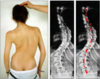

Décrire : Scoliose

Déviation latérale sur le plan frontal associée à une rotation